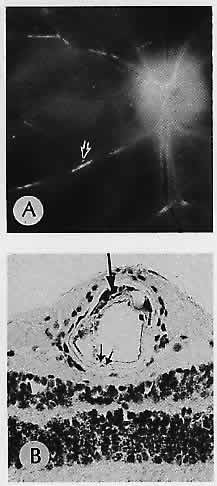

In contrast, occlusion of the central retinal artery or its branches results in ischemic infarction of the inner retinal layers. Usually, these occlusions are embolic, most commonly from calcific, platelet, and cholesterol emboli.25 Emboli can result from a variety of other causes including amniotic fluid, bacteria, air, cloth particles from prosthetic heart valves,28 and talc emboli in intravenous drug abusers.29 Nonembolic causes include atherosclerosis (Fig. 5) and inflammatory processes that narrow and occlude the lumen from swelling of the vascular walls, such as cranial arteritis, Wegener's granulomatosis, and collagen vascular diseases.

Fig. 5. Atherosclerosis. A. Gross appearance Of the fundus of an eye removed postmortem. Arrow indicates plaque in the inferonasal arteriole, seen microscopically in (B). B. Frozen section stained with oil red-O shows lipid deposits (arrow) in atheromatous plaque. Note the fatty infiltration in the muscular wall at the edge of the artifactitious cleft (double arrow). (A, macroscopic; B, oil red-O, ×200)

Cholesterol emboli are commonly seen in patients who have ulcerated atheromatous plaques of the carotid arteries. Often, however, these emboll do not occlude the vessel because their shape does not readily conform to the shape of the vessel. These are seen clinically as Hollenhorst plaques and appear as bright shiny yellow emboli within the vessels (Fig. 6).30